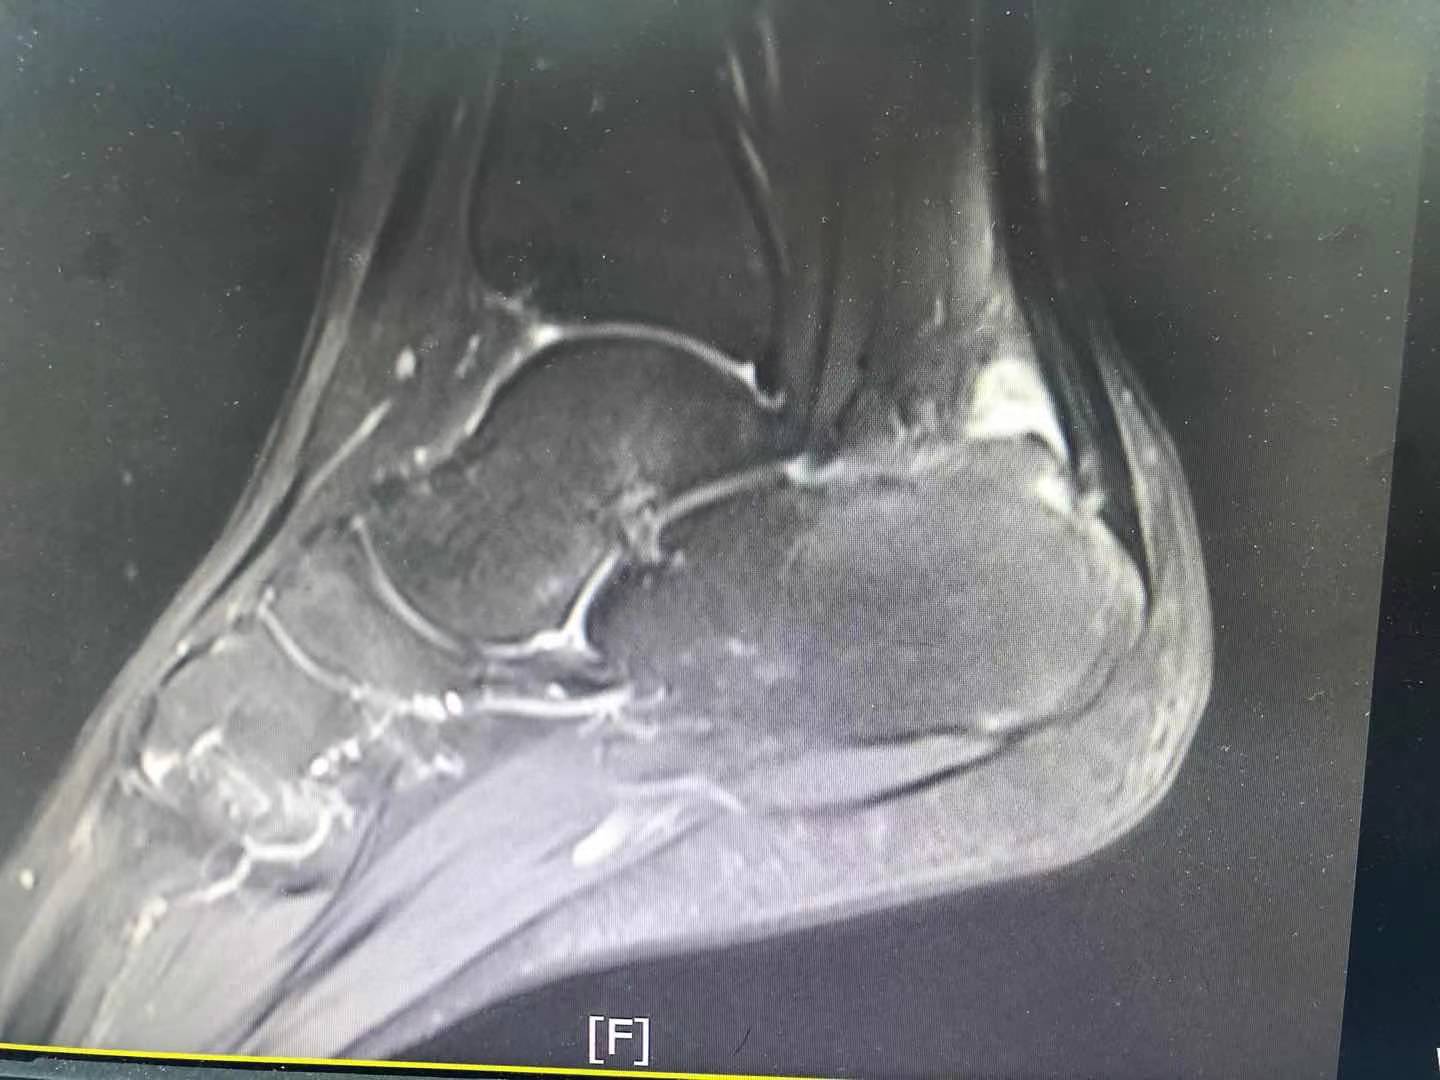

近日,曲靖市第一人民医院关节与运动医学科在关节镜下为跟痛症患者进行跟骨后滑囊炎清理、跟骨成形术,术后患者恢复良好,这是该科首次将关节镜技术应用于足踝患处。

16岁的女性患者董某,受右足后跟疼痛困扰2年多,站立行走时疼痛加剧,她已经2年没有参加过学校的体育锻炼,长期服用止痛药物,严重影响学习生活,曾到多家医院治疗,效果不佳,后到市一院关节与运动医学科就诊。收治入院后,市一院关节与运动医学科结合患者的治疗病史,积极展开讨论,决定采用微创手术方式治疗,在与患者及家属沟通病情和治疗方案后,由朱博主治医师、李超峰医师等在关节镜下行跟骨成形术、跟骨后滑囊炎清理术,术中对增生的跟骨后上缘进行切除并打磨平整,对跟腱周围炎性组织进行清理,手术顺利完成,术后患者疼痛明显缓解。

跟痛症是以足跟部疼痛命名的疾病,主要病因是跟骨结节周围慢性劳损引起的疼痛及行走困难,常伴随跟骨骨质增生改变,如跟骨后上方增生、跟骨骨刺等。对一些保守治疗后长期不愈的跟痛症患者,采用微创手术治疗是很好的选择。微创关节镜手术切口小,术中出血少,对关节影响小,并发症少,术后恢复快,是关节与运动医学领域理想的诊断与微创手术治疗方式。